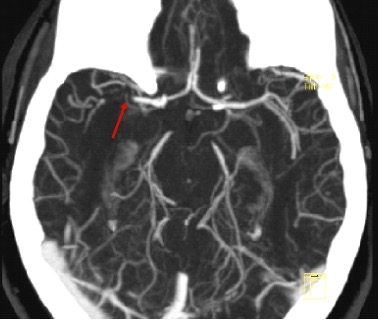

CT angiogram is useful in identifying LVO to select patients who may be candidates for endovascular therapy. This could be useful in patients with a high NIHSS = 7-10 to evaluate for LVO and 11-14 may require thrombectomy. It helps determine how accessible the clot is. Not all centers do these routinely on all stroke patients. More than the risk of renal injury (0.04%) is the risk of allergy.

Multiphase CTA has three sets of pictures: an arterial, venous (8s later) and late venous phase (16s later) to check for collateral circulation, important in prognosis.

MR angiograms can find occlusions and stenoses, evaluate the cranial circulation without the use of IV contrast. This is useful for identifying secondary causes of ICH like vascular abnormalities (aneurysms, AVMs). The time-of-flight 3D reconstructions are affected by motion artifact, by the patient but even blood flow. They can overestimate vessel stenosis.